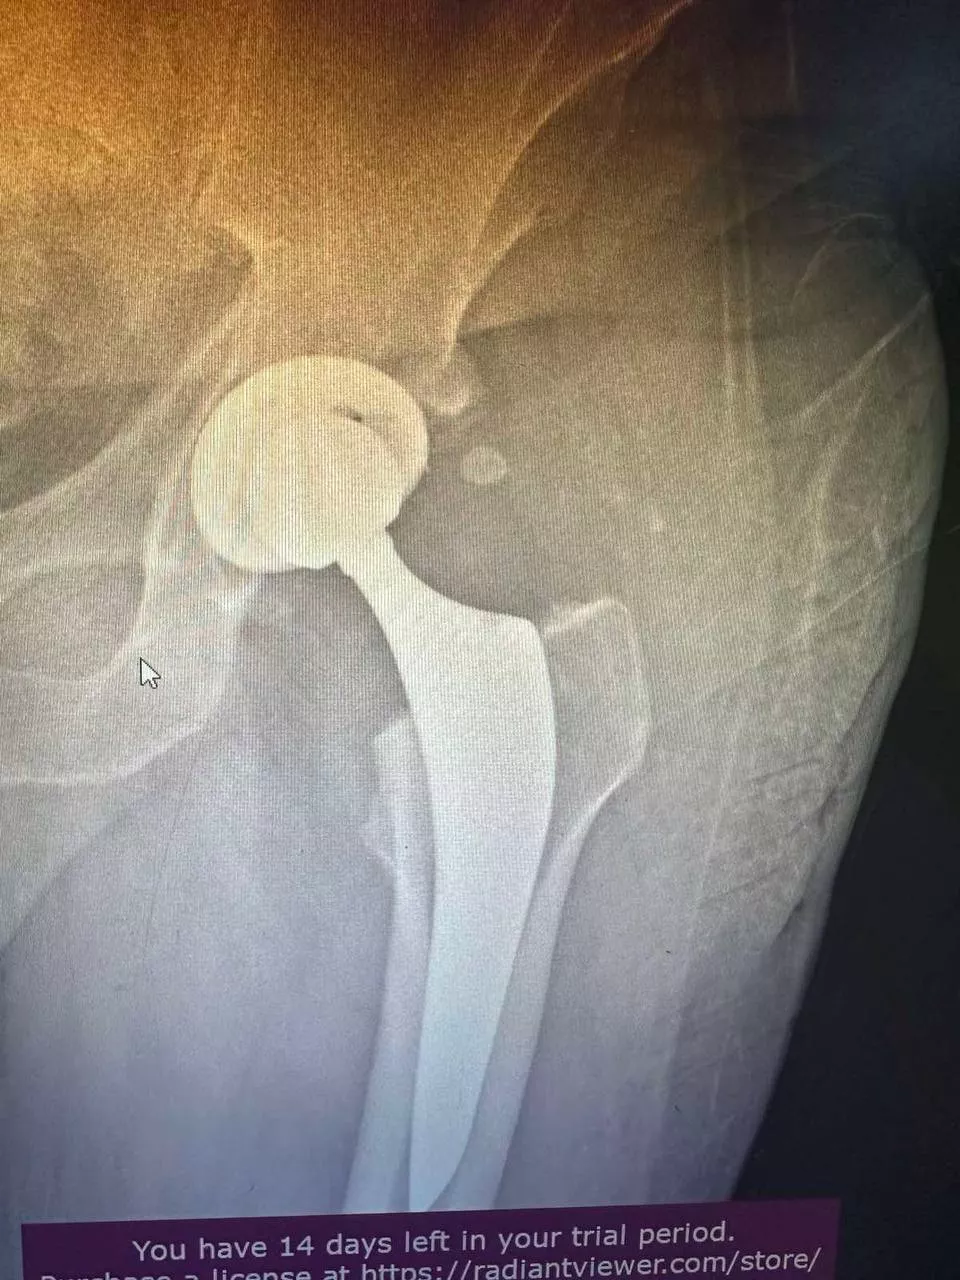

Ендопротезування кульшового суглоба

Заміна кульшового суглоба — одна з найефективніших операцій, яка вважається "золотим стандартом" в ортопедії. Цей вид хірургічного втручання виконується для лікування важких захворювань суглобів і відновлення їхньої рухливості. Під час операції пошкоджений суглоб замінюється на штучний імплантат, що дає змогу значно зменшити біль і повернути свободу рухів. Ендопротезування допомагає відновити повноцінне функціонування кульшового суглоба, забезпечуючи пацієнту активне і комфортне життя.